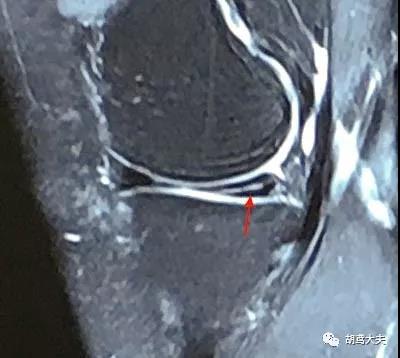

她的片子是这样的:

注意她的半月板后角里有一条白色的线(红箭头所指)

如果半月板撕裂了,关节中的关节液就会渗入到裂隙中,核磁上半月板里就会出现和关节腔相连的这种白色的细线。

由此看来,她确实是有半月板撕裂。